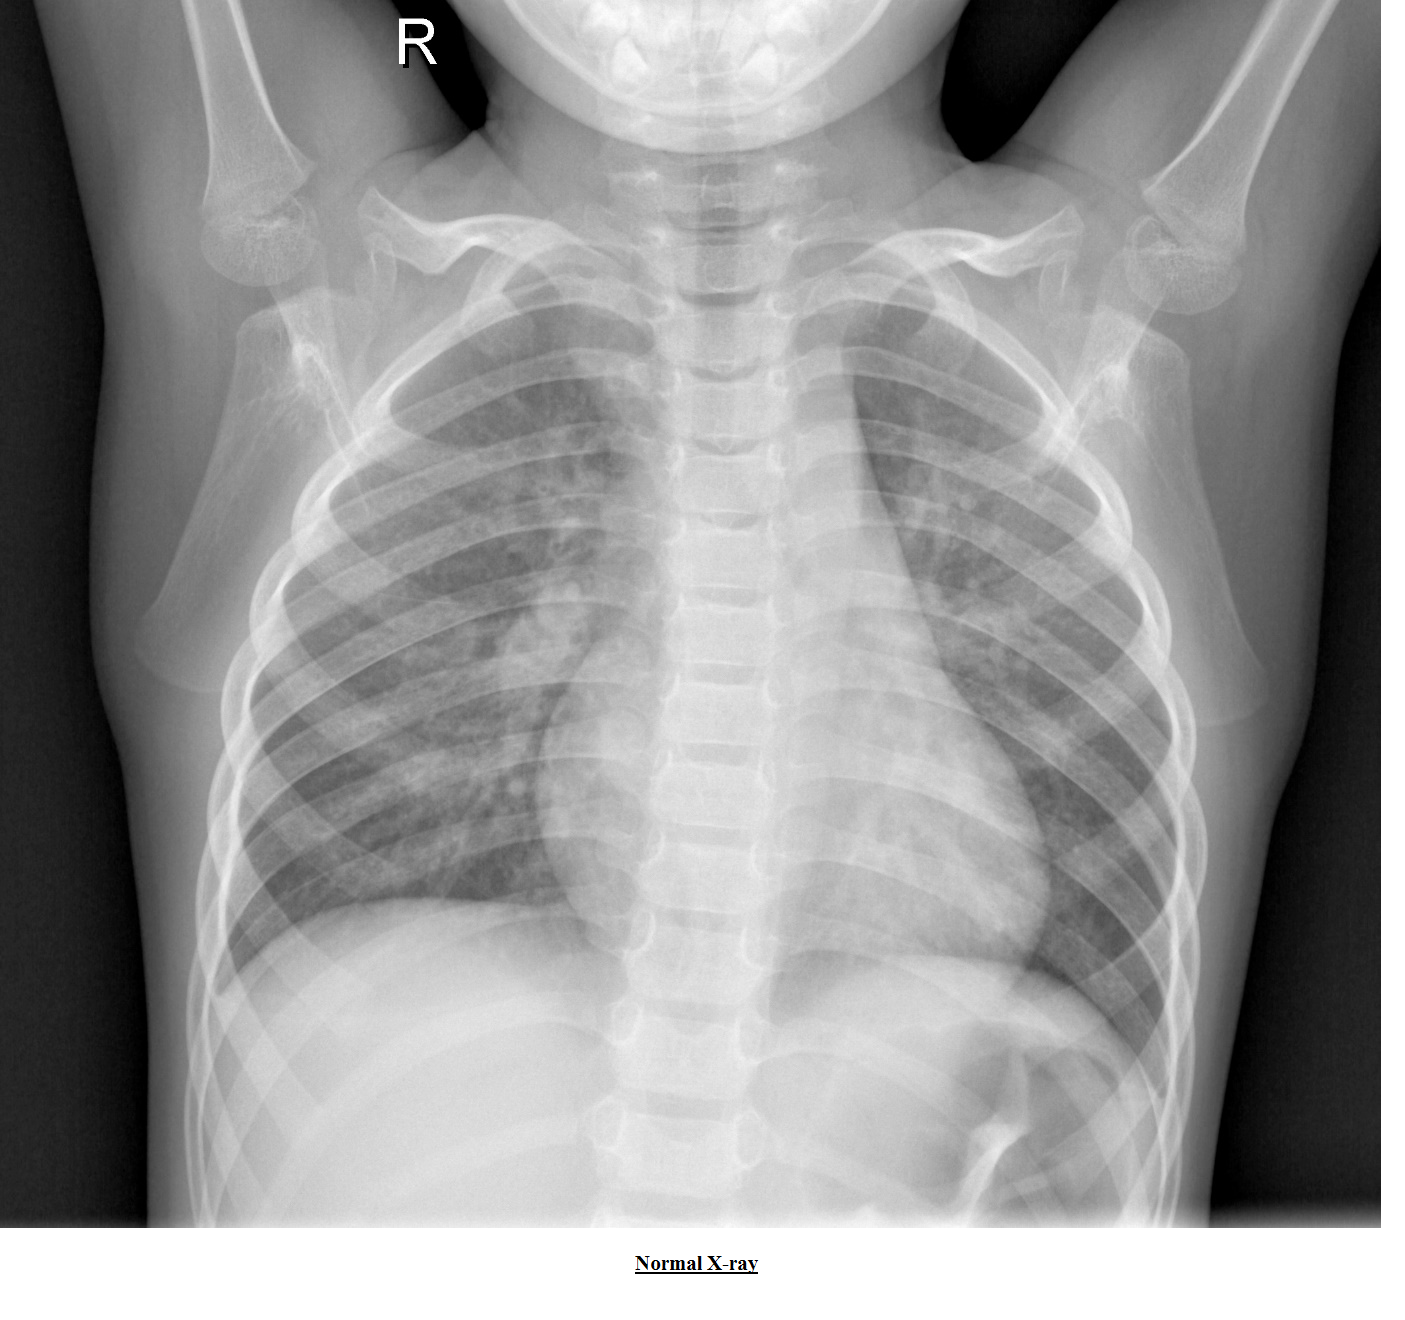

4. Pneumonia detection using x-rays

The input is various X-ray images. The X-ray images are classified into abnormal and normal. Due to less number of images, the image augmentation is done to boost the performance of CNN.